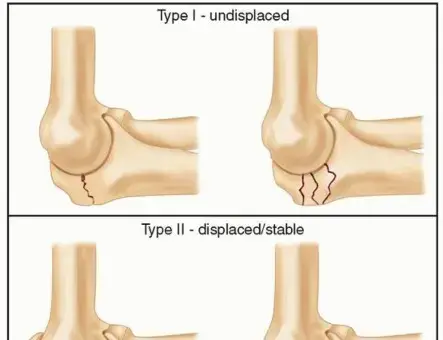

تعد كسور الزج في المرفق من الإصابات الشائعة في الطرف العلوي، حيث تشكل ما يقرب من 1-2% من جميع الكسور ونسبة كبيرة من كسور المرفق. الزج هو الجزء البارز من عظم الزند في المرفق، ويشكل مكونًا حيويًا في مفصل المرفق، حيث يتصل بالبكرة العضدية (تروكليا العضد) ليمنح المرفق استقراره ويعمل كذراع رافعة لعضلة ثلاثية الرؤوس القوية. غالبًا ما تحدث كسور الزج نتيجة لصدمة مباشرة، مثل السقوط على المرفق، أو صدمة غير مباشرة، غالبًا ما تكون إصابة قلعية ناجمة عن انقباض مفاجئ وقوي لعضلة ثلاثية الرؤوس بينما يكون المرفق في وضع شبه مثني. تصيب هذه الإصابات البالغين بشكل أساسي، مع توزيع ثنائي الذروة يبلغ ذروته لدى الشباب النشطين ومرة أخرى لدى كبار السن بسبب السقوط منخفض الطاقة المرتبط بهشاشة العظام.

- تساعد الأشعة السينية في تصنيف الكسر (مثل تصنيف مايو) بناءً على الإزاحة والتفتت واستقرار المرفق.

دواعي الاستطباب (متى يُنصح بها):

- الكسور المزاحة: إزاحة تزيد عن 2 ملم، خاصة إذا كانت تشمل السطح المفصلي.

- عدم تطابق السطح المفصلي: أي عدم استواء أو "درجة" في السطح المفصلي تزيد عن 2 ملم، مما قد يؤدي إلى التهاب المفاصل ما بعد الصدمة.

- كسور الزج المستعرضة: هي الأنسب لهذه التقنية.

- كسور الزج المائلة القصيرة: التي يمكن تثبيتها بأسلاك K.

- بعض الكسور المفتتة: عندما يكون التفتت أساسًا في القشرة الظهرية غير المفصلية، وتوجد شظايا عظمية كافية ومستقرة لدعم أسلاك K واستقرار البناء.